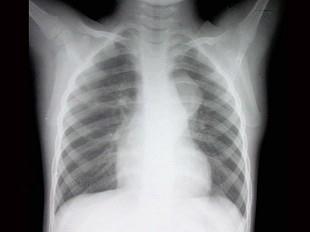

女,4岁,根据影像图像,最可能的诊断是?(?)A.肺癌B.胸骨后甲状腺肿C.胸腺瘤D.神经源性肿瘤E.淋巴瘤

问题 女,4岁,根据影像图像,最可能的诊断是?(?)

选项 A.肺癌 B.胸骨后甲状腺肿 C.胸腺瘤 D.神经源性肿瘤 E.淋巴瘤

答案 D